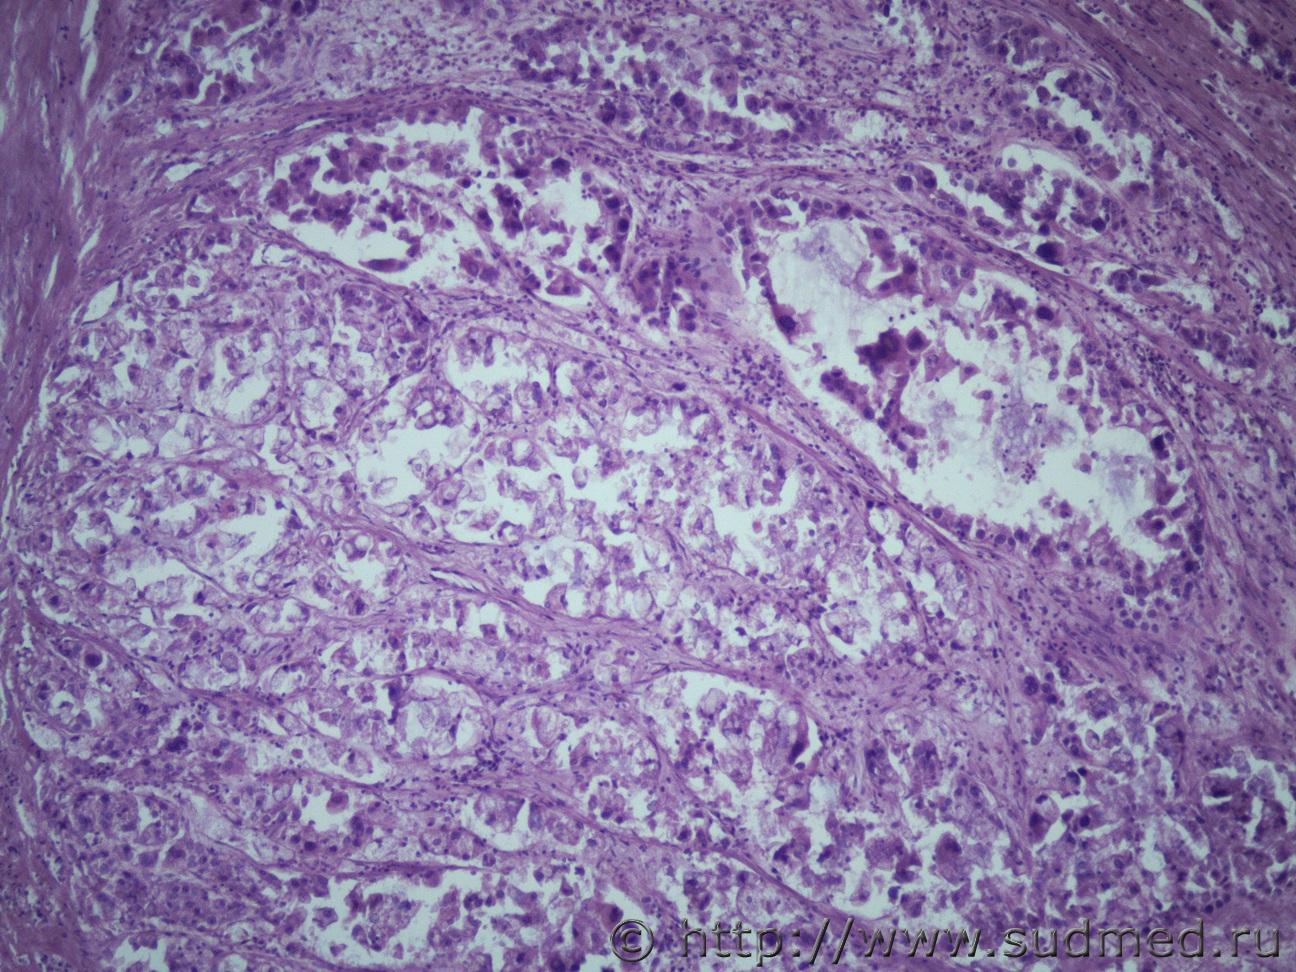

Ув. коллеги нужна помощь. Муж 60 лет. Эксперт присылает злокачественное новообразование левой почки с метастазами в правую почку и легкие. В стеклах опухоль в почке над капсулой (какая это почка правая или левая не указано) Судебная медицина - Прикрепленное изображение Судебная медицина - Прикрепленное изображениеСудебная медицина - Прикрепленное изображениеСудебная медицина - Прикрепленное изображениеСудебная медицина - Прикрепленное изображение

По мне - железистый вариант гипернефроидного рака.

Гипернефроидный рак.

Почечно медуллярная карцинома с mts в легкие